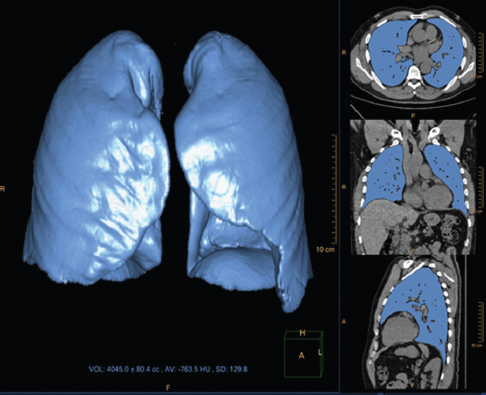

Lung volume parenchyma and airway volumes were measured by quantitative volumetric analysis [Figure 2] on the CTPA imaging sequence using the Philips IntelliSpace lung segmentation software (v6.0.3.12200, Best, The Netherlands).